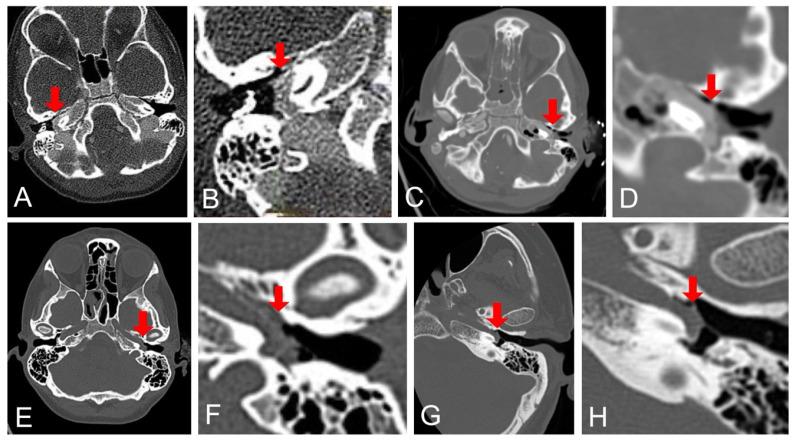

An aberrant internal carotid artery (aICA) in the middle ear is a rare vascular anomaly with potentially catastrophic consequences if injured during otologic procedures. Given its rarity, standardized treatment recommendations are lacking. This study aims to present four cases of aICA bleeding, systematically review the literature, and evaluate the outcomes of conservative and interventional management. A retrospective review of four patients treated for intraoperative aICA hemorrhage at two tertiary referral centers was performed. A systematic review was conducted following PRISMA guidelines. Neurologic and otologic outcomes, hemostasis, and complications were analyzed. Two patients were treated conservatively with external auditory canal packing, while two required endovascular coil embolization due to pseudoaneurysm formation or persistent bleeding. One patient suffered a stroke due to traumatic ICA occlusion. The systematic review identified 20 additional cases. Conservative treatment alone sufficed in 37.5% of cases, whereas 62.5% required vessel occlusion via coiling, balloon occlusion, or stenting. Neurologic complications occurred in 25% of patients, while otologic outcomes varied widely and were inconsistently reported. Initial external auditory canal packing and a CT angiogram should be recommended for all patients. Initial conservative management may be appropriate for cases with early hemostasis if close monitoring is ensured. Endovascular treatment is often necessary, particularly in cases of pseudoaneurysm or rebleeding.

中耳内的异常颈内动脉(aICA)是一种罕见的血管异常,如果在耳科手术中受伤可能会导致灾难性后果。鉴于其罕见性,缺乏标准化的治疗建议。本研究旨在呈现4例aICA出血病例,系统回顾文献,并评估保守治疗和介入治疗的结果。对在两个三级转诊中心接受术中aICA出血治疗的4例患者进行了回顾性研究。按照PRISMA指南进行了系统回顾。分析了神经和耳科结局、止血情况及并发症。2例患者采用外耳道填塞进行保守治疗,另外2例因假性动脉瘤形成或持续出血而需要进行血管内线圈栓塞。1例患者因外伤性颈内动脉闭塞而发生中风。系统回顾又发现了另外20例病例。仅保守治疗在37.5%的病例中就足够了,而62.5%的病例需要通过线圈栓塞、球囊闭塞或支架置入来闭塞血管。25%的患者发生了神经并发症,而耳科结局差异很大且报告不一致。应建议所有患者首先进行外耳道填塞和CT血管造影。如果能确保密切监测,初始保守治疗可能适用于早期止血的病例。血管内治疗通常是必要的,特别是在假性动脉瘤或再出血的病例中。